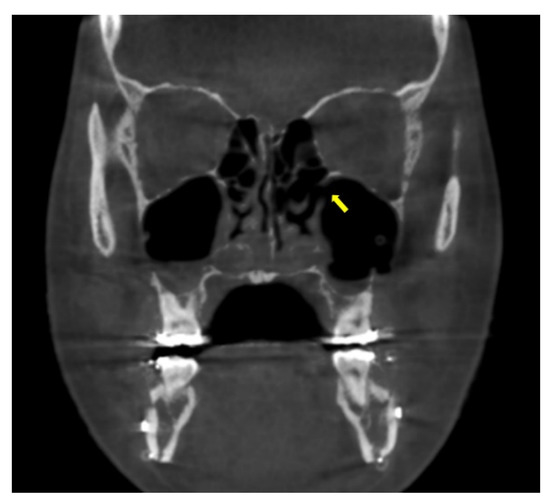

Questions may arise as to whether the bony holes drilled to apply the MSVD will heal completely with time. We observed that drilled bony holes had become smaller during the metal removal surgery at 2 years after bimaxillary orthognathic surgery (Figure 7). These remaining bony defects did not clinically affect the physiology or function of the maxillary sinus. At the last follow up, 4 years after the procedure, there were no other sino-nasal clinical symptoms or complications regarding the MSVD. All tubes should be removed the day after operation to prevent the active post-operative bleeding. According to our experience, there was no case of late bleeding in the group of patients with MSVD. However, it is important to alertly monitor for late bleeding.

Figure 7.

The drilled bony holes for the maxillary sinus ventilation drainage had become smaller (arrows) at 2 years after the bimaxillary orthognathic surgery.